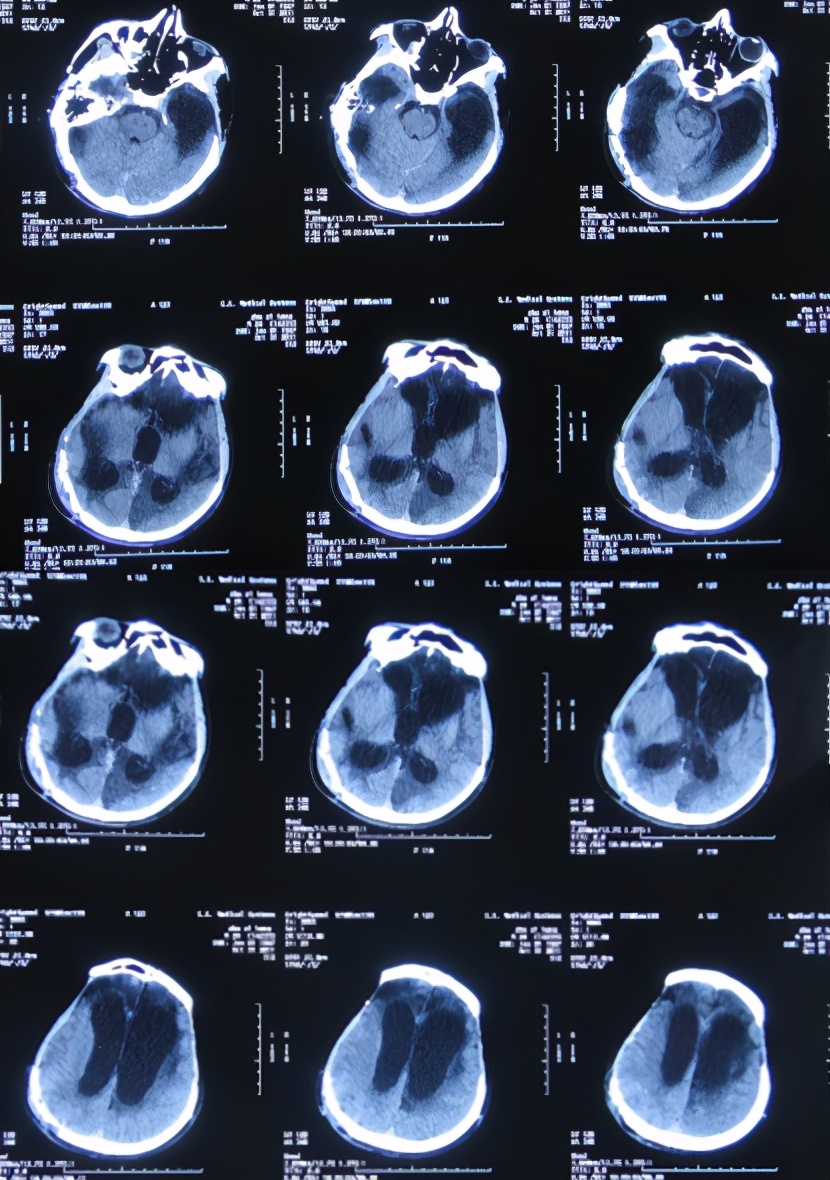

开颅术后185天即2011年7月19日(干细胞移植治疗84天后),患者病情不见好转,反而更重:不能遵嘱活动,已不能简单言语,头颅CT示脑积水仍没有改善( 图-7 )。

图-7: 2011年7月19日头颅CT

第4家医院治疗87天即开颅术后289天即2011年10月31日,因脑积水始终未得到满意治疗;期间还外请更高级的北京某三甲知名医院的专家会诊,但此专家看完头颅CT后( 图-8 )建议暂时不做腹腔分流术,因为他断定:“做了分流术之后,患者也不可能好转!”。

图-8: 2011年10月31日头颅CT

入院时:昏迷状态,刺激无发音,能自动睁眼但肢体不能遵嘱动作,不能吞咽吃饭。头部情况:双侧额颞部去骨瓣减压术后颅骨缺损,头皮手术瘢痕未见异常渗出,骨窗大小约7*8cm,头皮凹陷;头颅CT(外院2011年10月31日)提示脑外伤术后,脑积水。但右侧原手术刀口经久近1年不愈合,以往几家医院均认为除了自愈之外没有好的治疗方法。

入院后3天即2011年11月10日,术前例行头颅CT( 图-10 )检查后,行侧脑室外引流术。

图-10: 2011年11月10日头颅CT